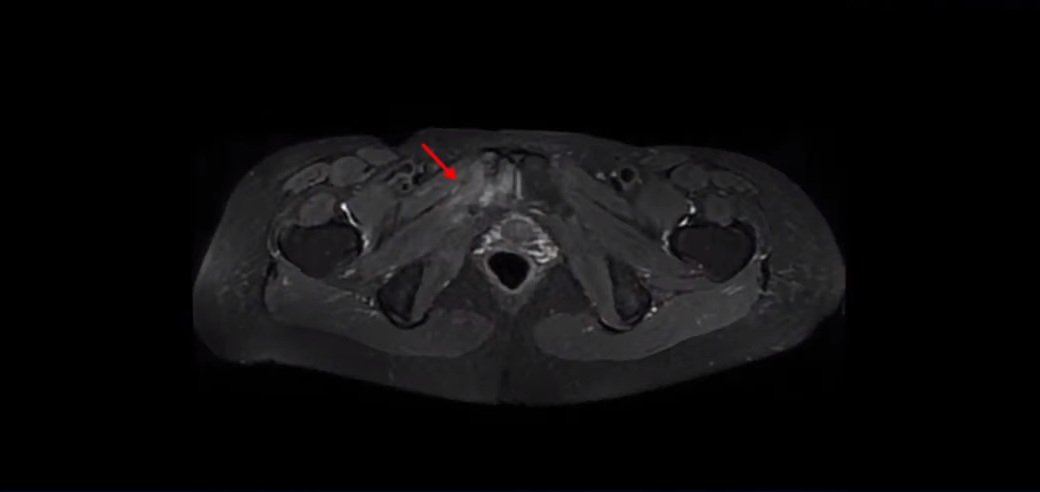

제가 이 환자분의 MRI를 보면서 먼저 설명 드리고 그 이후에 이 환자분의 이야기를 직접 들어 보시겠습니다.

이 환자분은 아주 심하게 넘어지면서 엉덩이 근육이 파열되고 고관절에 미세 골절이 발생한 분입니다.